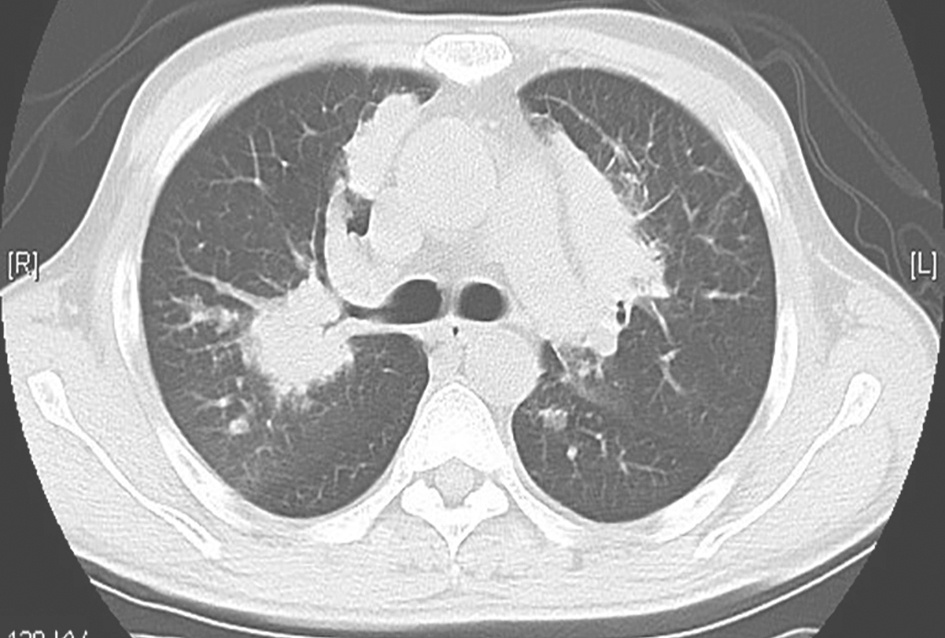

胸部CT平扫和增强扫描示:双肺多发结节及肿块高密度影;纵隔内可见淋巴结轻度增大,无融合趋势(图1)。

图1 胸部CT平扫和增强影像

双肺弥漫多发结节及肿块高密度影(A~F);纵隔内部分淋巴结轻度增大(D~F),无融合趋势

4.影像学检查显示双肺弥漫性多发结节和肿块,上肺明显,局部病灶有小空洞,纵隔内淋巴结无明显肿大,肺内病灶增强后无明显强化。